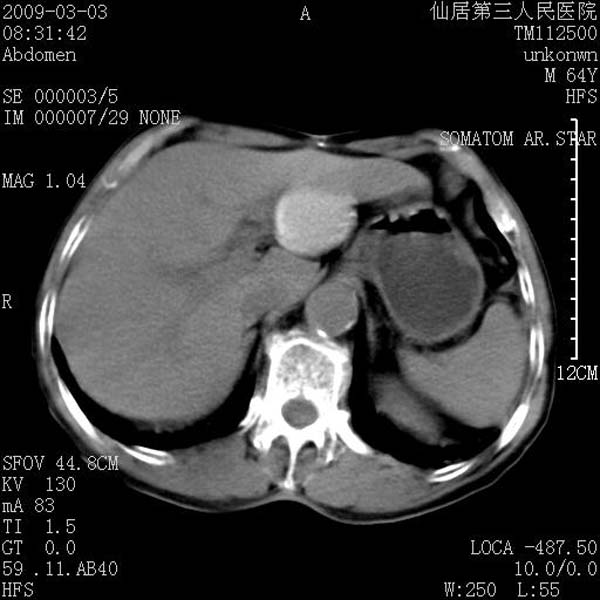

标题: CT18469:男性,64y,体检B超示肝脏低回声肿块,有胃溃疡手术 [打印本页]

患者,男性,64y,体检b超示肝脏低回声肿块,有胃溃疡手术史。

考虑----胃肠道间质瘤可能性大

从平扫及增强的特点来看,支持肝脏腺瘤并出血。

考虑胃间质瘤可能性大。

胃肠道间质瘤!

ct值呢?感觉没强化,象囊性。

考虑肝静脉韧带裂区良性占位性病变(囊肿?)。

考虑肝囊肿并出血可能性大.

考虑高密度囊肿可能性大